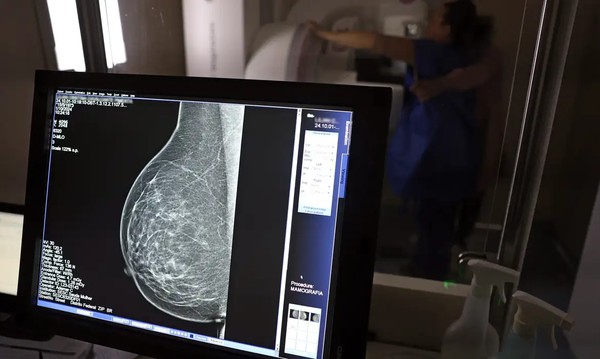

• Ministério da Saúde agora recomenda mamografia a partir dos 40 anos

Até o momento, a orientação era que o exame fosse feito depois dos 50 anos

O Ministério da Saúde passou a recomendar o acesso a mamografia, via Sistema Único de Saúde (SUS), para mulheres de 40 a 49 anos – mesmo que não haja sinais ou sintomas de câncer de mama. De acordo com a pasta, a faixa etária concentra 23% dos casos da doença, e a detecção precoce aumenta as chances de cura.

Até então, a orientação era que o exame fosse feito a partir dos 50 anos.

A medida faz parte de um conjunto de ações anunciadas nesta terça-feira (23) voltado para a melhoria do diagnóstico e da assistência. A recomendação para mulheres a partir dos 40 anos é que o exame seja feito sob demanda, em decisão conjunta com o profissional de saúde.

“A paciente deve ser orientada sobre os benefícios e desvantagens de fazer o rastreamento. Mulheres nesta idade tinham dificuldade com o exame na rede pública de saúde por conta da avaliação de histórico familiar ou necessidade de já apresentar sintomas”, informou o ministério em nota.

As mamografias via SUS em pacientes com menos de 50 anos, de acordo com a pasta, representam 30% do total, o equivalente a mais de 1 milhão apenas no ano de 2024.

Outra medida anunciada é a ampliação da faixa etária para o rastreamento ativo – quando a mamografia é solicitada de forma preventiva a cada dois anos. A idade limite, até então, era 69 anos. Agora, passa a ser 74 anos. Dados do ministério revelam que quase 60% dos casos de câncer de mama estão concentrados entre 50 e 74 anos.

Os números mostram que, em 2024, cerca de 4 milhões de mamografias para rastreamento e 376,7 mil exames diagnósticos foram realizados no SUS.